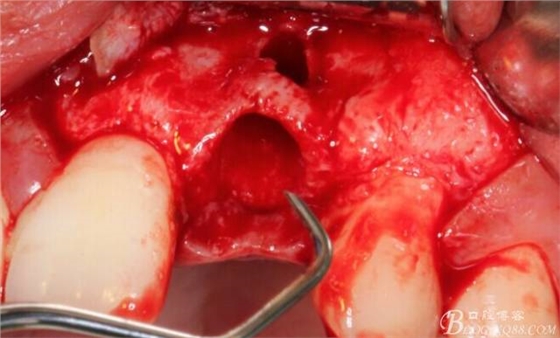

于是我果斷告知患者,手術(shù)失敗了,不能拖延,如不及時處理,炎癥繼續(xù)發(fā)展會很快波及鄰牙牙槽骨。患者接受我的建議。切開翻瓣,骨粉及生物膜消失了,骨吸收嚴(yán)重,幸運的是,因為處理及時,鄰牙骨支持依然存在。